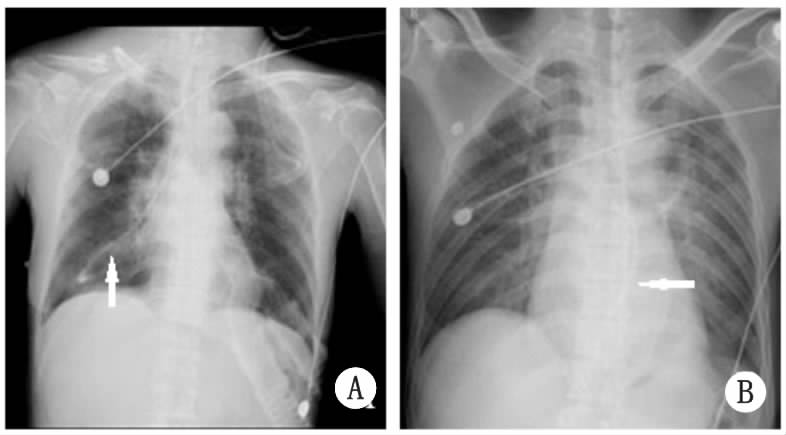

单中心双盲前瞻性研究。纳入研究的患者由一名具有成熟置管经验的住院医师采用常规盲插法置入鼻饲管,选复尔凯螺旋型鼻饲管(YZB/苏)内径CH10,长度145 cm(纽迪希亚医疗保健有限公司,荷兰)。超声法定位由另一名经过急危重症超声规范培训并有足够经验的临床医师(笔者本人)完成,操作前并不了解2种常规法定位的结果。患者取平卧位,使用Micro Maxx便携式超声机(SonoSite公司,美国)。颈部使用频率为6~13 MHz的直线线阵探头,在甲状腺峡部水平探查颈部,超声探头紧贴甲状腺左叶向中线区垂直扫查,食道横切面图像为规则圆形或椭圆形,不能被压扁、变形,内有空腔管道的回声或高回声的亮点,来回抽动鼻饲管时可见亮点回声移动。旋转探头获得食道长轴影像,可见鼻饲管的纵切面,为两条平行透亮高回声、呈“=”状。腹部换用频率为2~5 MHz的凸阵探头,在上腹部按照食道下段—贲门顺序探查鼻饲管,然后继续探查胃体—幽门、左腋中线处向中线区扫射胃底部查找,胃内可见两条平行透亮高回声、呈“=”形状的鼻饲管影像(图 1)。鼻饲管留置完毕2 h内进行床旁X线摄片,选用SM-50HF移动摄片机(赛德科公司,西班牙),由放射科技师按照规范获取胸部(含上腹部)的前后位摄片,放射科医师独立完成阅片并出具报告。结果判断参照英国NHS推荐的X线进行鼻饲管定位的标准[17](图 2)。

A:颈部超声扫查时探头的位置;B:腹部超声扫查时探头的体表位置;C:颈部的CT截面图,可见食道位于甲状腺左叶后内侧、气管左后方,食道内高密度亮点为鼻饲管;D:上腹部CT的截面图,贲门位于肝左叶后方、腹主动脉前方,贲门内高密度亮点为鼻饲管;E、G:颈部食道内的超声横截面和纵切图;F、H:胃贲门/胃体内鼻饲管超声图,受胃内气体干扰的鼻饲管只能部分显像。(Tr 气管;Th 甲状腺;E 食道;L 肝;G 胃) 图 1超声确定鼻饲管位置的方法